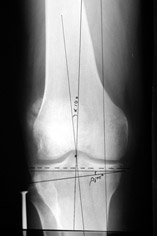

AVM> Александр, а не могли бы вы представить ваши схемы расчета? С учетом

Вот, с учетом и без учета, и на разных уровнях...

Саша Артемьев, может, для данного случая свой вариант нарисуешь?

AC> Вот, с учетом и без учета, и на разных уровнях...

AC> Саша Артемьев, может, для данного случая свой вариант нарисуешь?

Из приведнной схемы не совсеим понял что означают разноцветные линии.

И зачем латерализация периферического фрагмента. Я всегда делаю медиализацию. См схему. И для данного случая медиализация подходит как нельзя лучше.

a> Из приведнной схемы не совсеим понял что означают разноцветные линии.

Черные - это нынешняя механическая ось. Красные - это планируемая правильная ось.

a> И зачем латерализация периферического фрагмента.

;-) Читайте Палея. Стр. 114-115.

a> Я всегда делаю медиализацию. См схему. И для данного случая

Медиализация - это чисто эстетический прием, как я понимаю. Поскольку если делать остеотомию ниже вершины деформации, для восстановления оси надо делать смещение по ширине, в данном случае как раз латерализацию.

А вот на схемке без осей - там на разных уровнях (который правильнее?) устранение варуса чисто открытым клином без медиализации-латерализации. Если как-то так сделать - этого недостаточно будет?